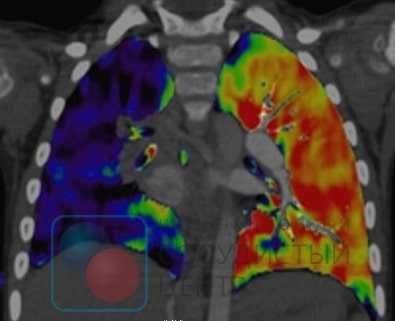

Вентиляционно-перфузионная сцинтиграфия легких является методом скрининга для исключения хронической тромбоэмболии как причины легочной гипертензии. У больных после тромбоэмболии обнаруживаются дефекты перфузии в долевых и сегментарных зонах при отсутствии нарушений вентиляции. Перфузионная сцинтиграфия исторически стала одним из первых методов обнаружения дефектов перфузии легочной паренхимы при ТЭЛА. Изображения, получаемые при острой ТЭЛА и ХТЭЛГ, существенно различаются. Дефекты перфузии при острой ТЭЛА более четко очерчены и резко контрастируют с нормально функционирующей тканью. При ХТЭЛГ дефекты перфузии очерчены не четко и часто не соответствуют зоне кровоснабжения крупной легочной артерии.